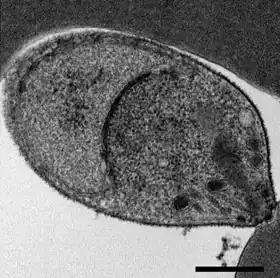

Die Leberschizonten produzieren Merozoiten, die freigesetzt werden und Erythrozyten befallen, wo eine weitere ungeschlechtliche Vermehrung stattfindet. Die Generationszeit bei der Vermehrung in den Erythrozyten beträgt ungefähr 24 Stunden und ist damit kürzer als bei allen anderen Malariaerregern der Primaten. Durch eine Synchronisierung der Entwicklung kommt es am Ende jedes Vermehrungszyklus zu einer massenhaften Freisetzung neuer Parasiten, die mit einem täglichen Fieberschub verbunden ist.